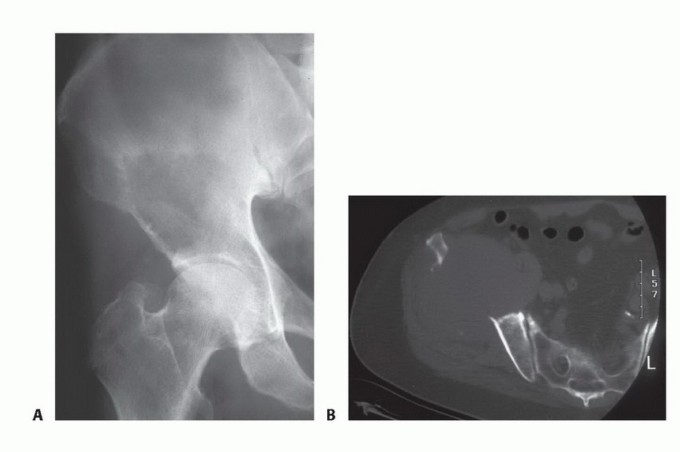

BACKGROUND Tumors involving the sacrum mainly include primary and metastatic tumors. Metastatic tumors are mo…